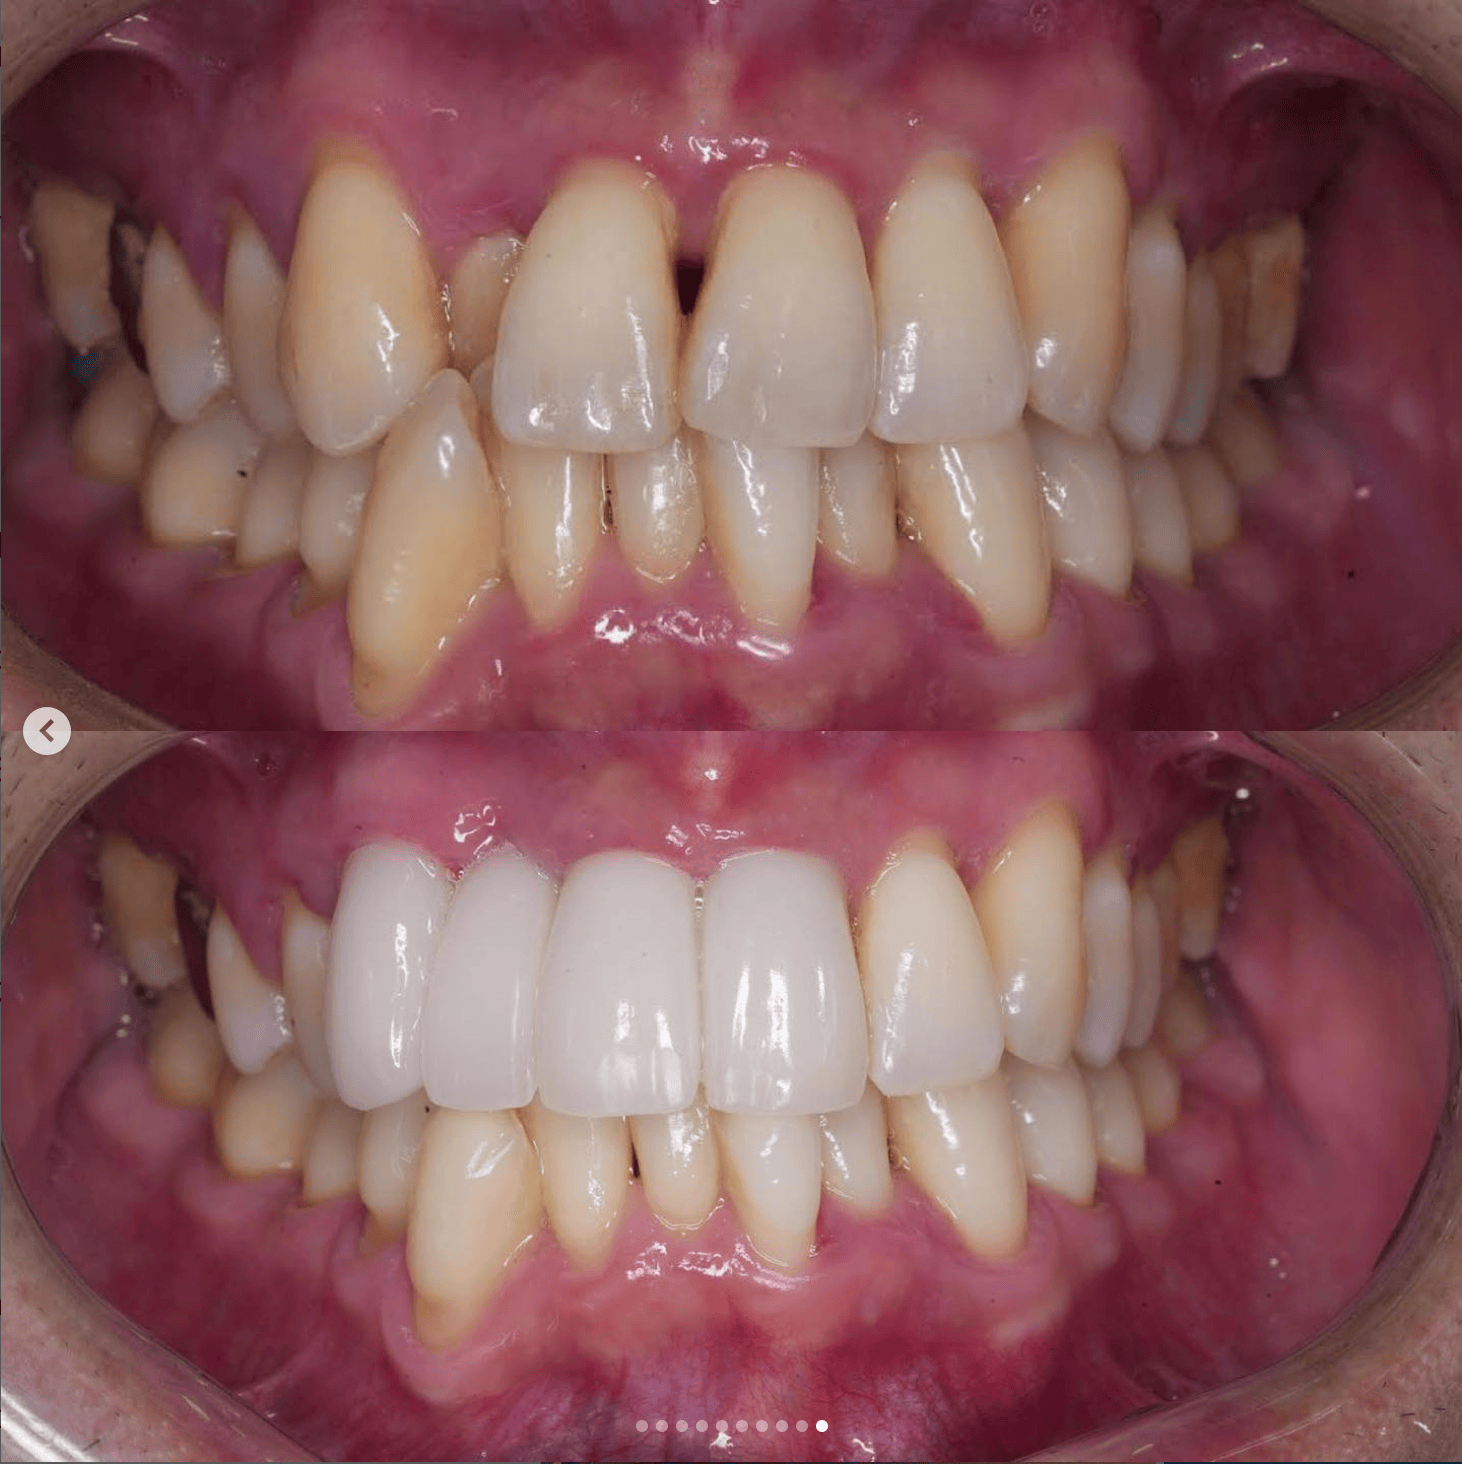

Case032

メジャーリーグでも活躍した元プロ野球選手の山口俊さんのセラミック治療を担当いたしました。

「他院で治療を受けたセラミックが欠けた」というのが主訴でしたが、よく診察するとセラミック欠けただけではなく、被せ物がしっかりと合っていないことが原因で歯茎の腫れがあり、歯石や汚れもつきやすい状態でした。また、歯列も若干歪んでいたので、この機会に全て治療いたしました。

治療後は透明感のある白さで、綺麗な歯並びになりました。また、セラミックをきちんと綺麗に削って適合よくセットしたことにより、歯茎の腫れも改善しました。

セラミックを入れた所の歯茎が腫れていて悩まれてる方はぜひご相談ください。

綺麗に削って適合よくセラミックをしてあげれば必ず改善します。